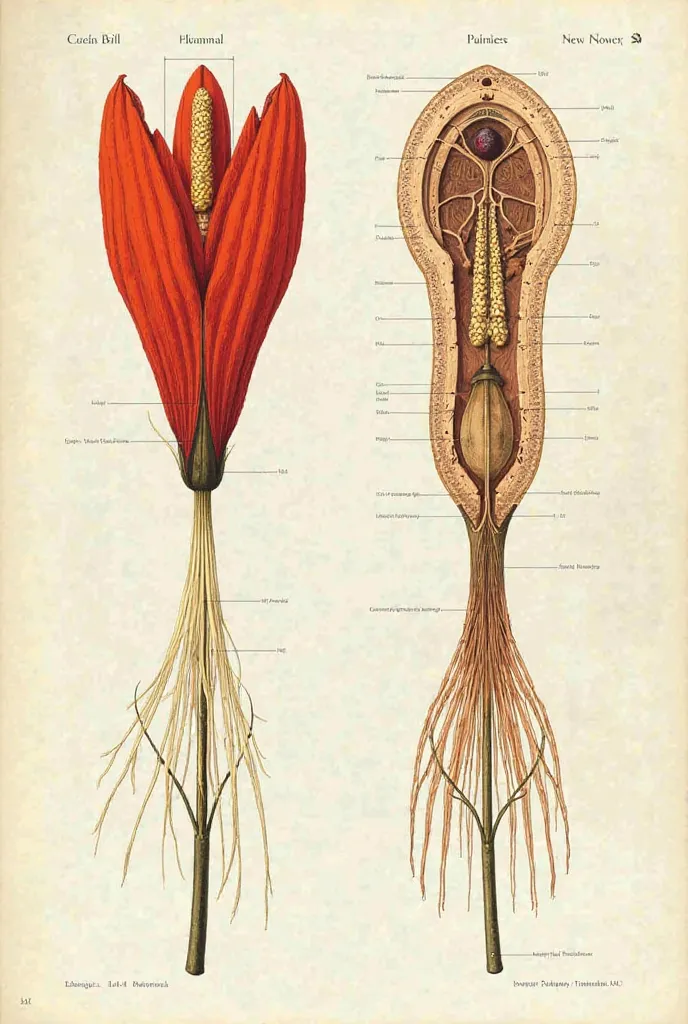

A diagram of the anatomy of the human body

Realice un dibujo de la piel. Coloque las siguientes referencias: Epidermis Fermis Hypodermis Keratinized squamous stratified epithelium Hair Sebaceous gland Sweat gland Pilo erector muscle Connective tissue Blood vessels Nerves Adipocytes

Epidermis Fermis Hypodermis Keratinized squamous stratified epithelium Hair Sebaceous gland Sweat gland Pilo erector muscle Connective tissue Blood vessels Nerves Adipocytes